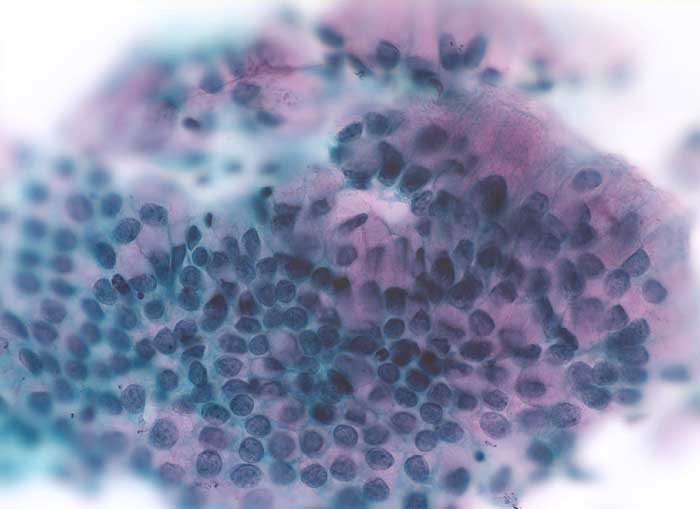

Endozervixzellen können unter Gestageneinfluss oder als Folge chronischer Reizzustände (Intrauterinpessar) Zellkernveränderungen wie beim endozervikalen Adenocarcinoma in situ ausbilden. Entsprechende klinische Angaben sind unabdingbar für die korrekte Interpretation dieser Veränderungen.